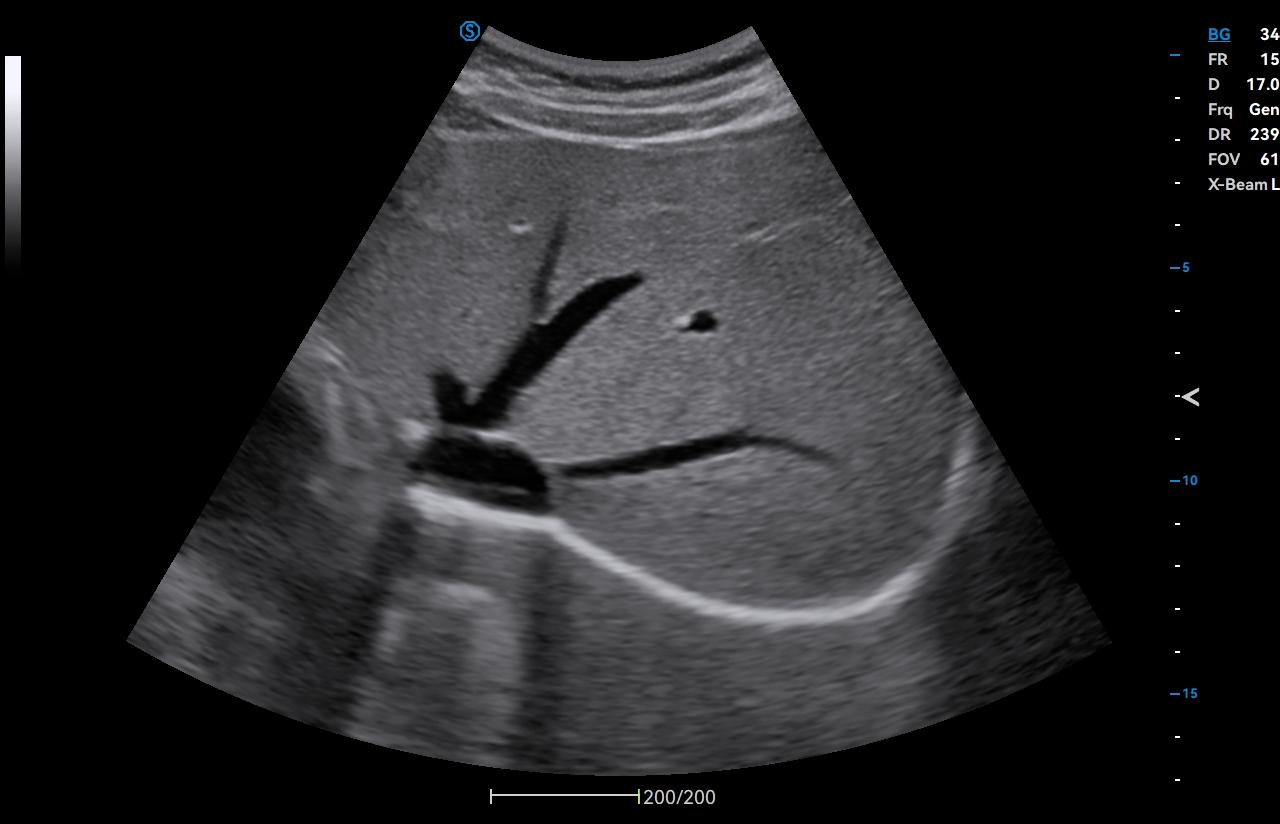

Full Volume Imaging and Coronal Section with High Clinical Value

IBUS acquires volume data from multiple sections to provide abundant information. The coronal section intuitively shows the anatomical information of breast tissue in a supine position during operation, which helps surgeon to perform more accurate surgical planning.